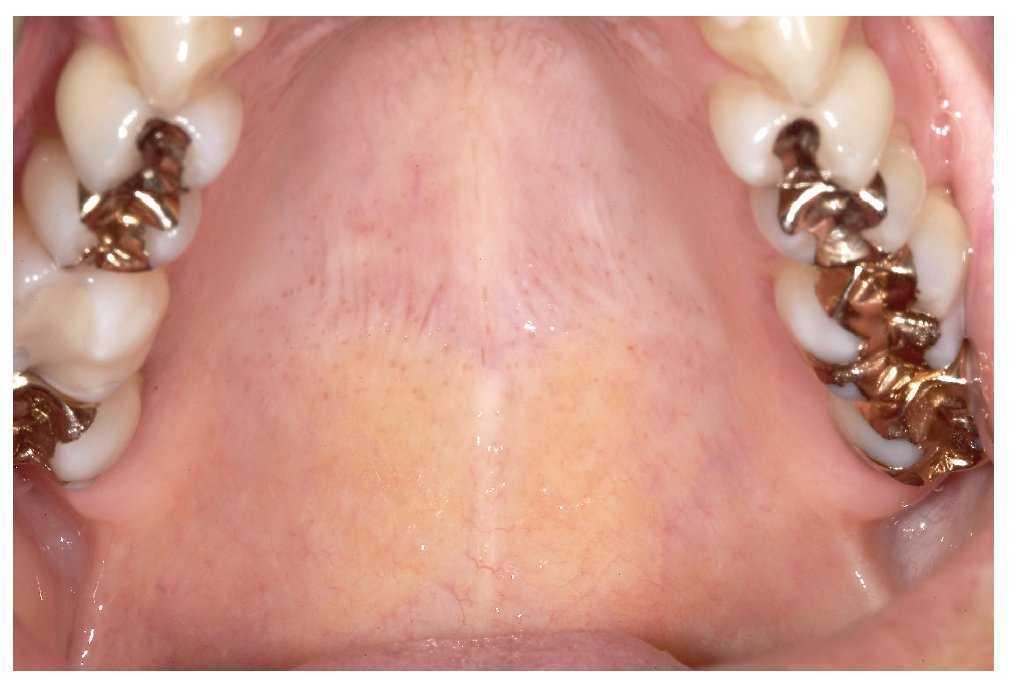

La mucosa del paladar blando y del paladar duro se inspecciona mediante visión directa con la cabeza del paciente inclinada hacia atrás (fig. 7). A continuación, se inspecciona el dorso de la lengua (fig. 8). Se puede sujetar y fijar la lengua con una gasa. Se exploran los bordes y la base de la lengua después de pedir al paciente que toque con la punta de la lengua el canino superior izquierdo o derecho (figs. 9 y 10). Esta maniobra permite explorar simultáneamente el suelo de la boca (fig. 11). La fijación de la lengua con una gasa facilita la inspección.

Figura 7. Después de explorar el borde del vestíbulo en la mandíbula se inspecciona el paladar del paciente.